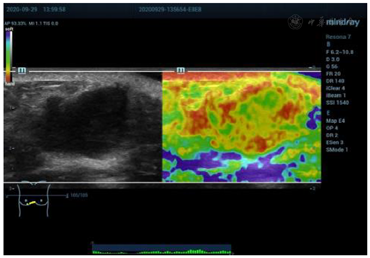

乳腺超声显示(图1):右侧乳腺5点半距乳头8~10 cm腺体边缘近胸骨旁扫见混合回声结节,大小约26 mm×15 mm,距体表6 mm,边界清晰,形态欠规则,内部回声欠均匀,后方回声略增强,CDFI:可见少许血流信号(图2)。弹性成像显示肿块硬度尚可(图3)诊断为BI-RADS 4a类,建议行乳腺超声造影。行超声造影后提示:增强早期肿块与周围乳腺组织相比,造影剂呈向心性、快进、高增强(图4),分布均匀,周边未见明显滋养血管,造影后范围30 mm×17 mm,大于二维超声;增强晚期造影剂缓慢消退,诊断为BI-RADS 4c类。